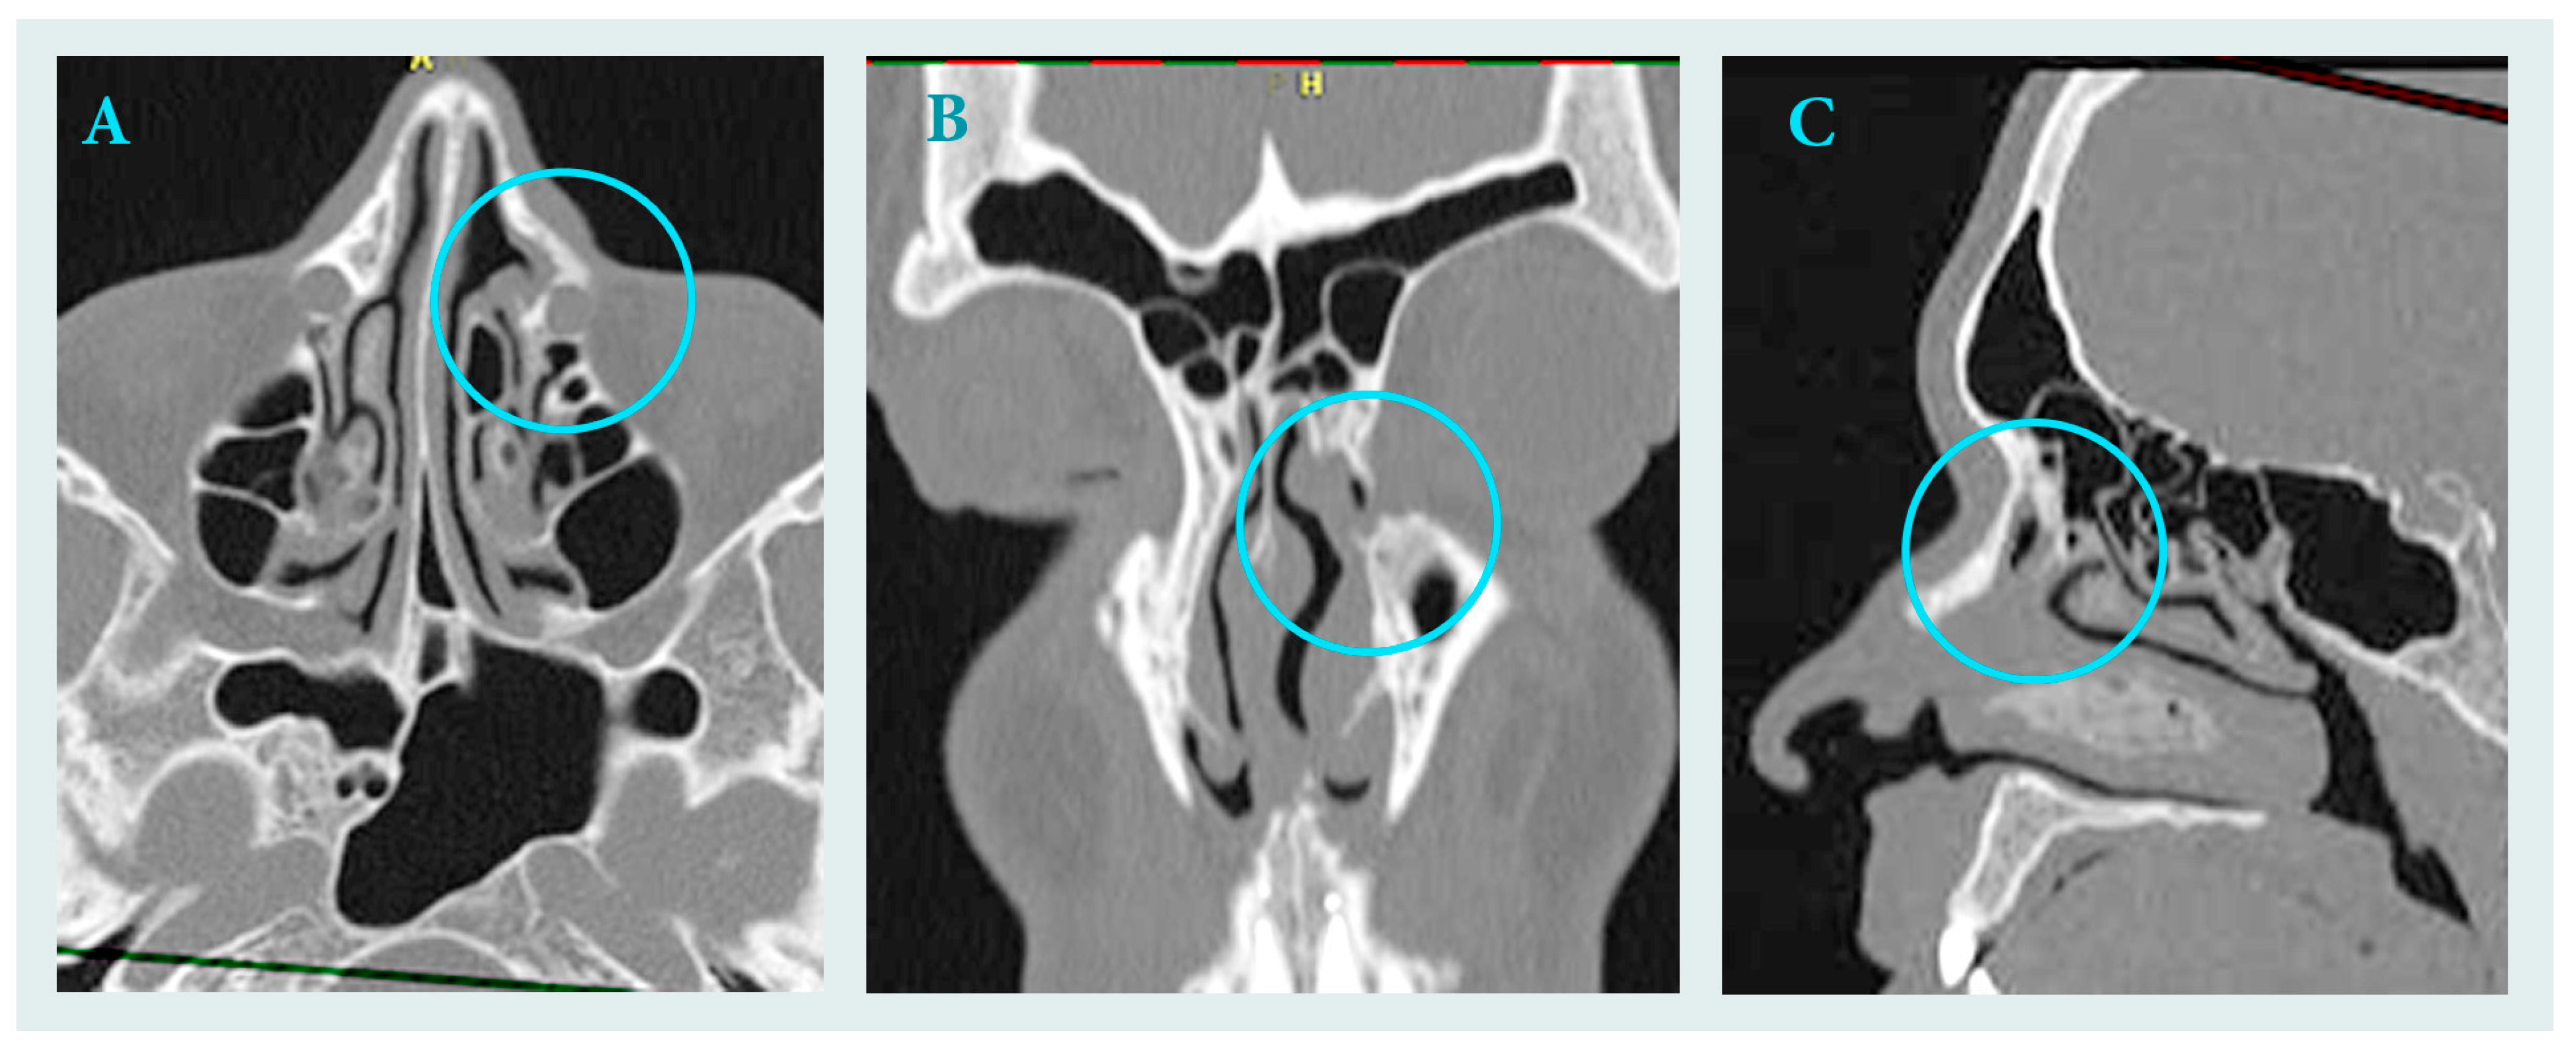

2.4. Follow up